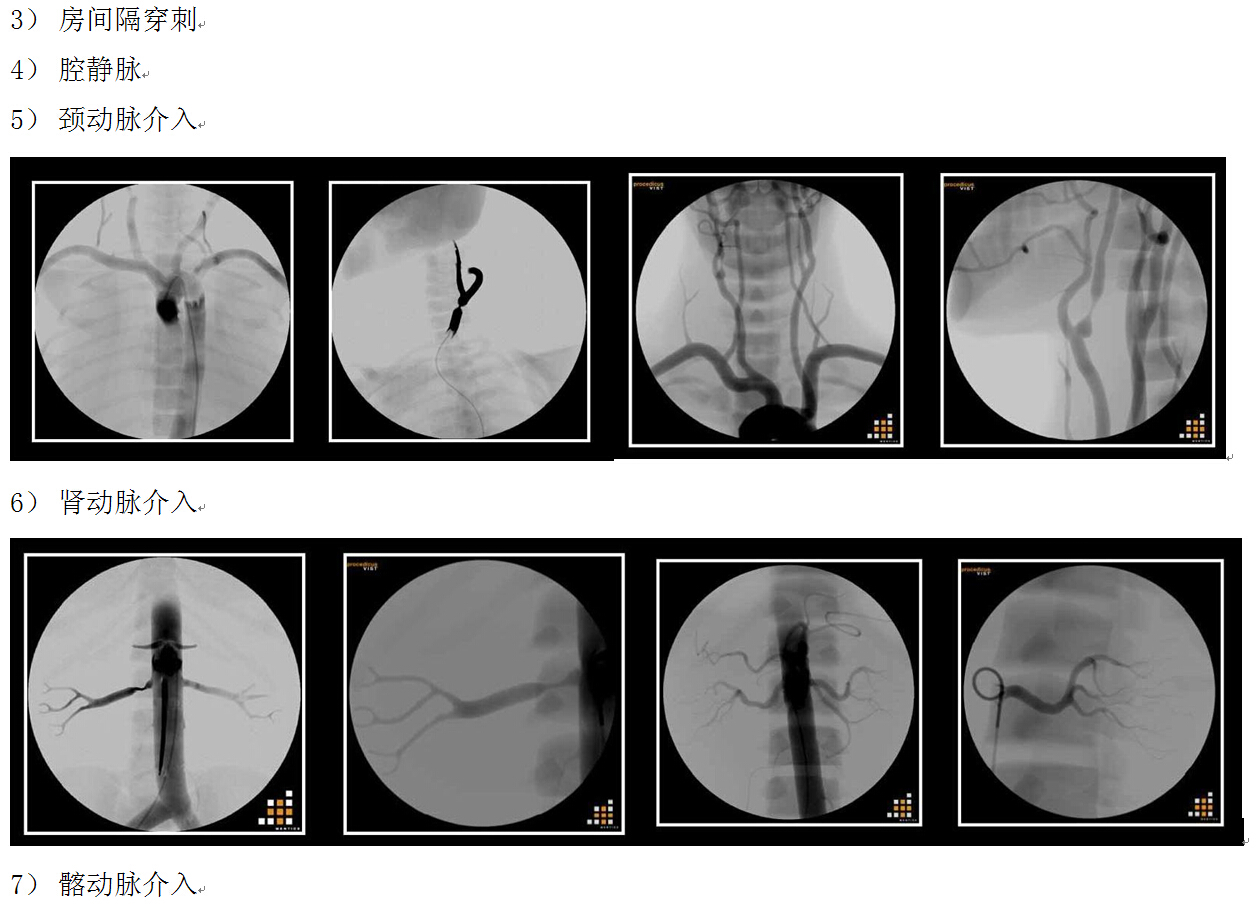

虛擬手術(shù)模擬器系統(tǒng)--血管介入手術(shù)模擬器

血管介入手術(shù)模擬器,Mentice

? Mentice VIST?C模擬器

是一便攜式高仿真血管介入手術(shù)模擬器, 對(duì)臨床醫(yī)生和醫(yī)療專(zhuān)業(yè)人員進(jìn)行動(dòng)手能力培訓(xùn),

● 在全物理模擬的支撐下,支持全面的血管造影術(shù)和介入培訓(xùn)手術(shù),實(shí)現(xiàn)了高度的模擬真實(shí)性。

● 這些模塊包含廣泛的培訓(xùn)情景,以驗(yàn)證學(xué)習(xí)者的技術(shù)技能、臨床決定能力和手術(shù)熟練度。